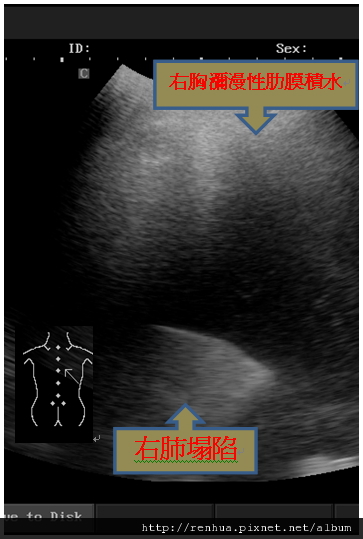

案例一 王先生,59歲, 30年老菸槍,咳嗽,喘氣10天。 診斷:右胸瀰漫性積水,右肺塌陷。